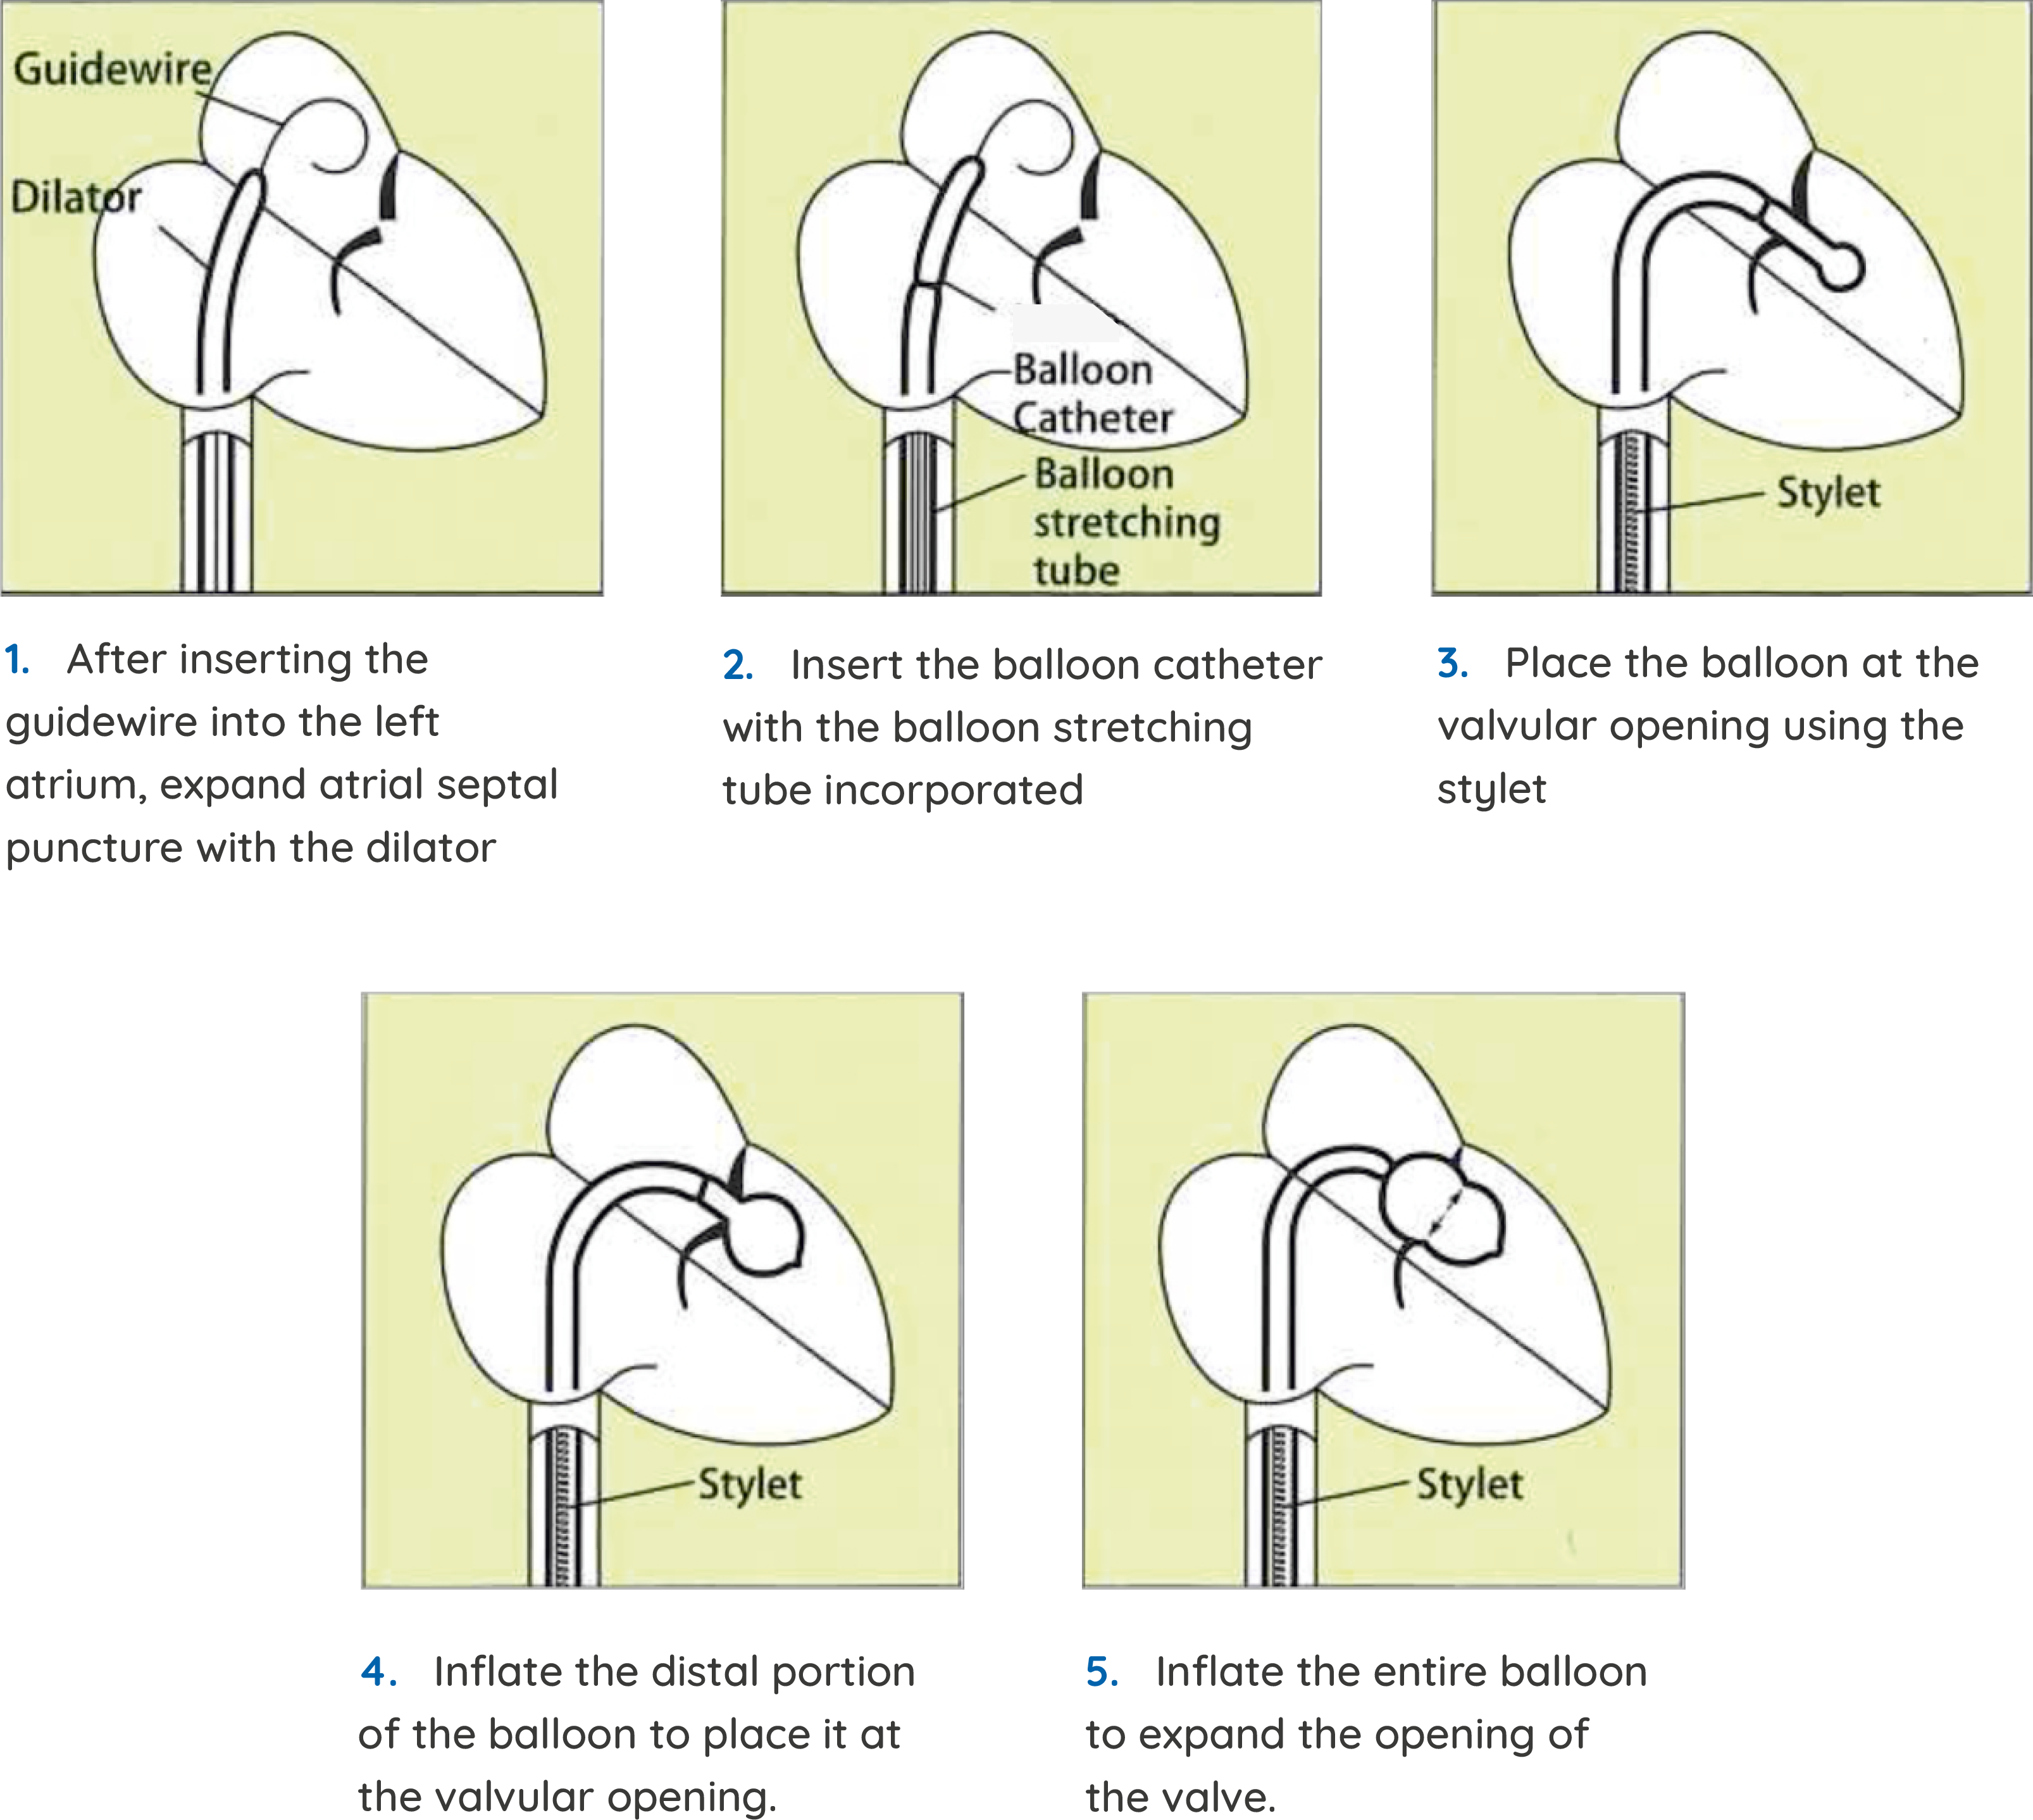

PBMV Balloon Catheter

SYM PBMV Balloon is specially designed to treat mitral valve stenosis.

Features

- Specially Designed balloon, Perfectly shaped to the mitral valve.

- A CE marked product

- Soft and small tip to avoid chances of perforations

- Made of Latex material for increased flexibility to ensure easy inflation and deflation.

- Longer length LA guidewire to increase safety in taller patients.

- 3rd Lumen for extra safety.

- Three Layer for better strength and support

- Economical prices